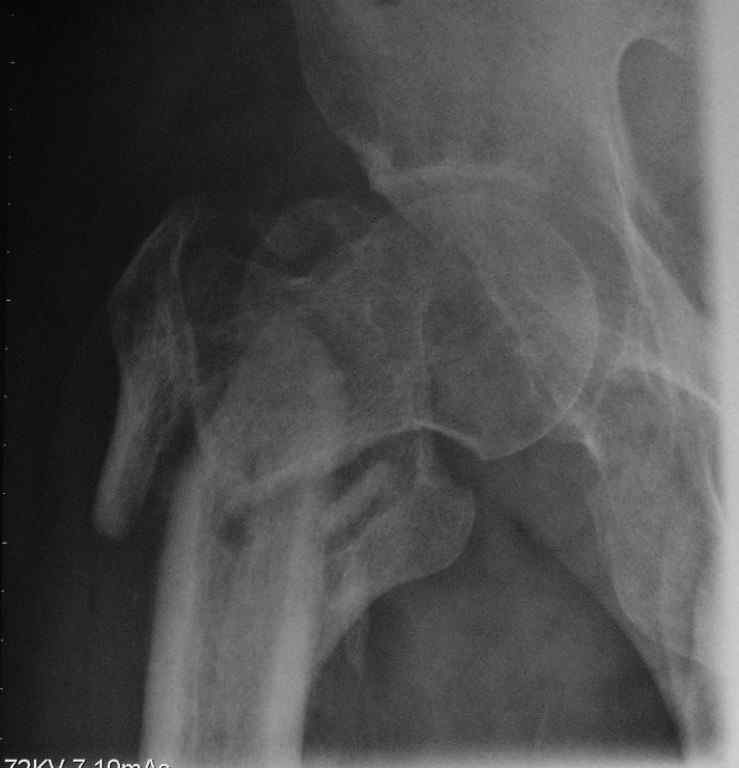

Пациент сорока лет с псевдартрозом правого бедра - исход оскольчатого чрезвертельного перелома с отрывом большого и малого вертелов. Поступил через 8 месяцев после травмы. По месту жительства лечили следующим образом: 2 месяца скелетное вытяжение, затем 2 месяца в кокситной повязке. После снятия гипса дали нагрузку. В настоящий момент имеется укорочение 6 см. Патологическая подвижность. По данным КТ - сращения нет, имеется аваскулярный некроз головки 2 стадии. В данном случае показано эндопротезирование тазобедренного сустава. Просим уважаемых коллег ответить на вопросы, которые возникли у нас по этому больному: 1. Имеет ли смысл выполнять первым этапом остеосинтез псевдартроза, учитывая, что нагрузка на сустав при наличии АНГБ противопоказана? 2. Возможно ли технически сразу выполнить эндопротезирование при наличии такого псевдартроза?

Вопрос в другом. 1) этот снимок не выглядит , как укорочение на 6 см. не понимаю

Форма головки сохранена, перелом, так скажем. не самый угрожающий в отношении ее "фатального" некроза.

Если имеются данные изотопного сканирования, кстати при начальных этапах это не всегда дает 100% результат, можно было бы выставить. А то на рентгенограмме не видно явлений, указывающих на АВН.

зачем такая категоричность?,КТ признаки аваскулярного некроза могут остаться диагностической находкой, импрессионного перелома нет. Остеосинтез проксимальным гвоздем через аппарат вполне может решить проблему несращения и укорочения. В дальнейшем, других операций может и не потребоваться.Даже если представить себе, что АВН будет прогрессировать, выполнить эндопротезирование будет гораздо проще после восстановления проксимального отдела бедра, ревизионные ножки скорее всего не потребуются.